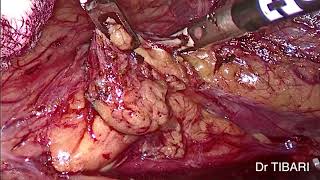

Nephrectomie coelioscopie video

Nephrectomie coelioscopie

Nephrectomie coelioscopie